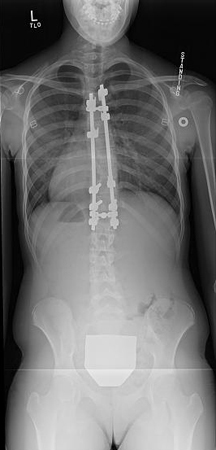

Thirteen-year-old girl post-posterior spinal instrumentation and fusion for progressive scoliosis

From the collection of Stuart Weinstein, MD, University of Iowa; used with permission